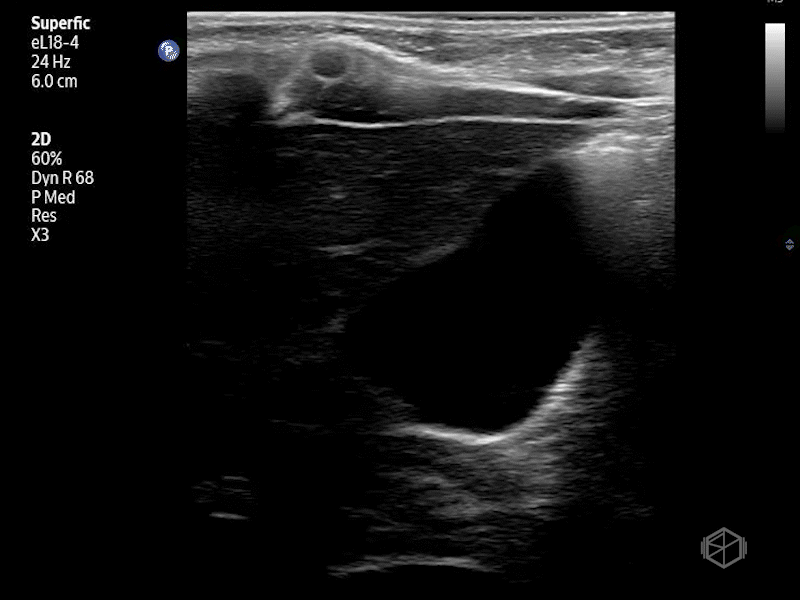

On their scan they saw:

Bedside abdominal ultrasound revealed: A “target” (donut) like structure in the right upper quadrant on transverse view. Concentric hypoechoic and hyperechoic rings representing telescoped bowel. A “pseudokidney” sign on longitudinal view. Bowel-within-bowel configuration measuring >2cm in diameter. No obvious free fluid was noted.

Diagnosis: Ileo-colic intussusception